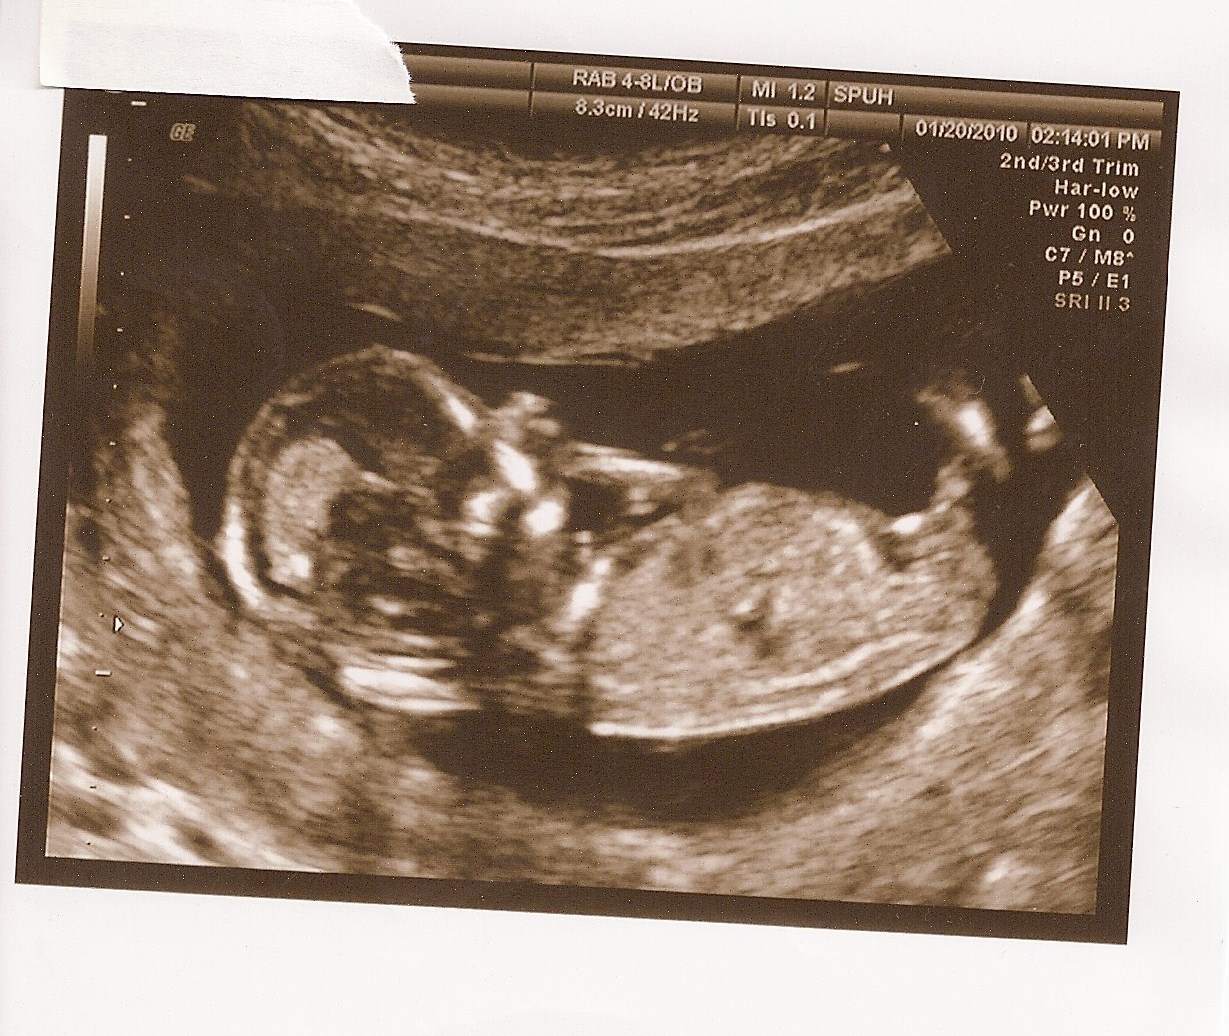

I have to admit, I was becoming really annoyed with my little duchess in my belly. Unlike her brother, she’s decided to stay put inside literally until she’s ready to come out. Sonny Boy was over 2 weeks early and I was ecstatic to let him out. At 7 pounds and 10 ounces, he was a chore to carry around during the last month. This is quite different from duchess.

So far, the docs see her as a petite bebe, weighing around 5 or 6 pounds. With out earlier scare, this made me even more nervous to hear, since her brother was larger. But, my own Mother reminded me that I was only 5 pounds 6 ounces and my sister was only 5 pounds 9 ounces, so she’s just following suit. Once I got past that worry, I started to anticipate her arrival around 3 weeks ago. I just KNEW she was gonna get here early since all the signs were here and I was feeling like utter poop. Well, Nope! She wasn’t ready and she was making sure I understood that. She did try to make an arrival a few weeks back, but since everyone but her agreed that it was too early, she was bullied into staying in. Now, she’s bullying back. Well, I’m now seeing that maybe she was right to stay in.